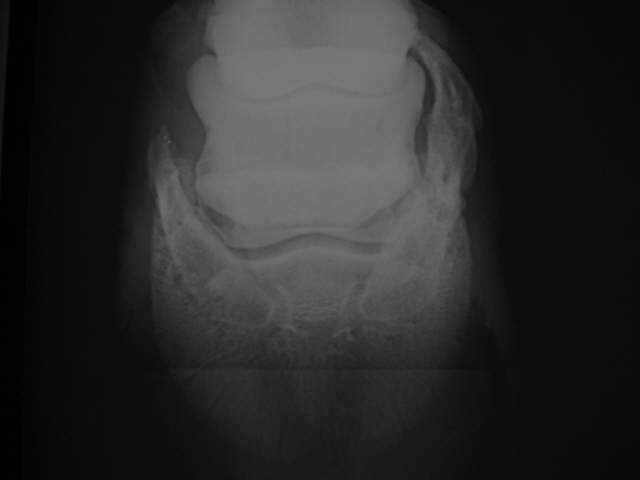

Hufknorpelverknöcherung